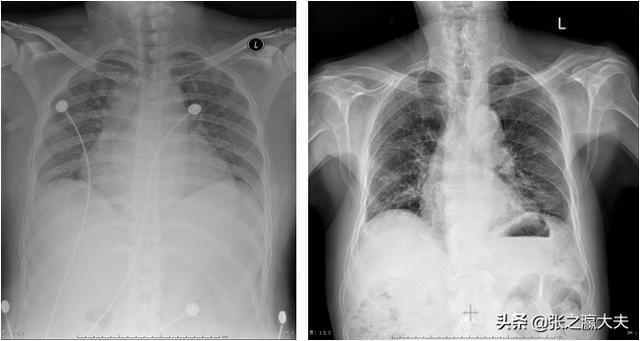

2.最も一般的な呼吸器疾患は、肺炎、気管支炎、結核、気管支拡張に起因する可能性があり、胸痛に加えて、これらはまた、痰、特に深い吸入の一部を咳に表示されます、咳は胸と腹壁の痛みを引き起こすでしょう。

胸痛が多いのは、呼吸器疾患では慢性閉塞性肺疾患、自然気胸、肺炎、気管支炎など、消化器疾患では逆流性食道炎、十二指腸潰瘍、胆嚢炎など、循環器疾患では心膜炎、心臓弁膜症、大動脈瘤など、神経疾患ではうつ病、心臓神経症など、胸が痛む可能性が多いからです。帯状疱疹、頸椎症、五十肩などの胸壁や関節系の病気。これらの病気に罹患している人は、狭心症とは定義できない胸痛症状を示すことがある。